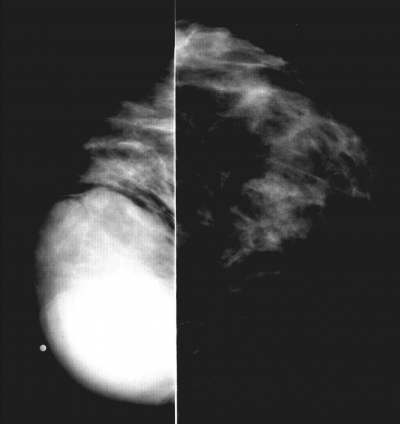

אבחון רנטגני

הניסיון הרנטגני באבחון סרקומת השד מצומצם. לשאתות הללו יש מספר מאפיינים רנטגניים: הן הומוגניות, בעלות צפיפות גדולה, מוגדרות היטב, וללא הסננה לסביבה (תצלום 34.12). כדי להבדילן מכיסות (ציסטות), יש להוסיף על הבדיקה הממוגרפית גם בדיקת אולטרה סאונד. מעקב ממוגרפי בפרקי זמן קצובים יבדיל בינן לפיברואדנומה עקב הצמיחה המהירה יותר של סרקומת השד.